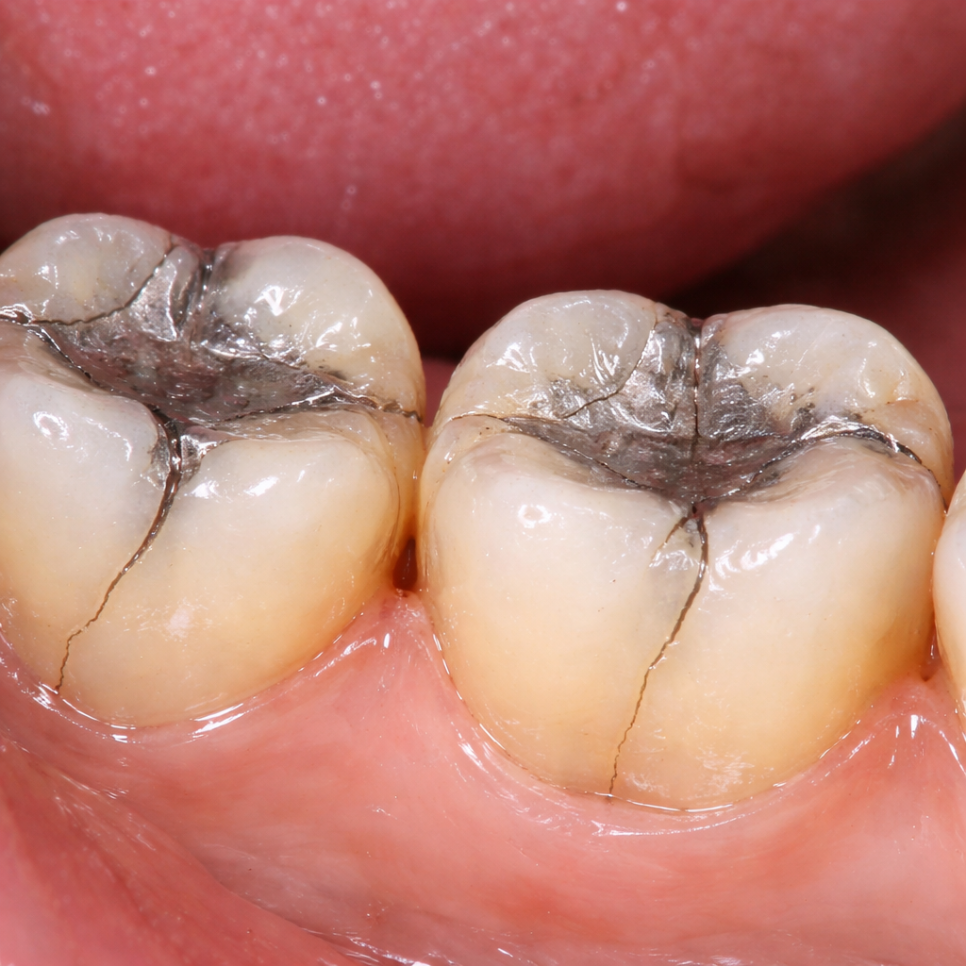

크거나 오래된 충전물이 있는 자연치는

온도 변화에 따라 미세하게 팽창·수축하면서

균열에 더 취약해지기도 합니다.

발산동 치과 구강 정보

CTS가 까다로운 이유는

일반 X-ray로는 균열선이

거의 포착되지 않는다는 점에 있습니다.

이해를 돕기 위한 치아 균열 예시입니다.

균열의 방향이 방사선이

투과하는 방향과 평행할 경우

영상에 나타나지 않기 때문입니다.